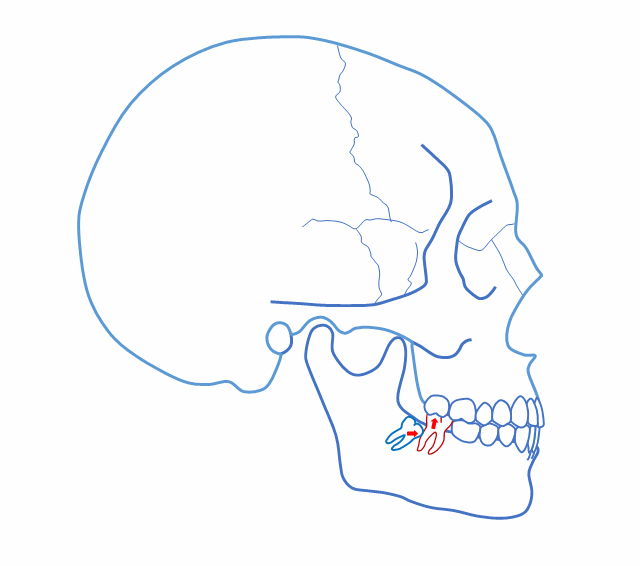

完全埋在牙槽骨里的下頜智齒,它本身倒是不出問題。但是這些近中或水平阻生的智齒,會推擠下頜第二磨牙,導致第二磨牙伸長:

0.gif

然后,第二磨牙造成咬合干擾、早接觸,前牙開 牙合…………

甚至髁突吸收:

所以,這種智齒也還是要 拔掉。